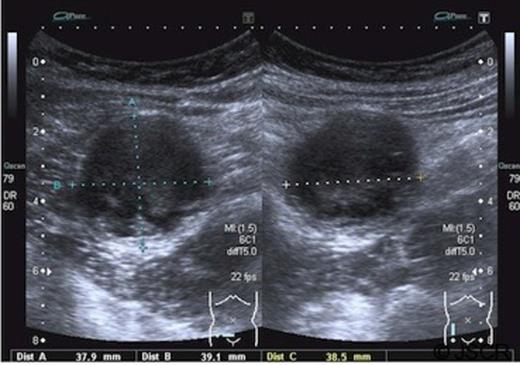

An eleven year old boy presented to the accident and emergency department complaining of pain in the lower abdomen. Initially his signs and symptoms were felt to be consistent with a non-specific cause. He re-presented a week later with persistent localised pain in the right iliac fossa and was noted to have a tender palpable mass, suggestive of appendicular pathology. A full blood count and C-reactive protein were normal. An ultrasound revealed a cystic lesion measuring 38mm by 39mm by 38mm in the right iliac fossa containing complex debris. The wall of the cyst appeared to be multilayered, possibly consistent with a duplication cyst. The appendix was not visualised.(Figure 1)

Ultrasound images showing a spherical cystic lesion with layering within

Ultrasound imaging identified a cystic lesion, but was not able to differentiate it from the more commonly presenting lymphangiomas and duplication cysts.